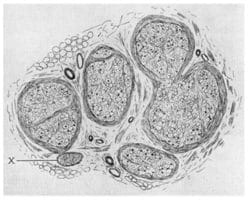

1986

Machleder, Moll, and Verity

First histologic examination of the anterior scalene muscle. Machleder, Moll and Verity demonstrate microscopic transformation of the anterior scalene muscle in patients with TOS. They find an increase in the muscle fibers that cause slow-twitch, prolonged contraction, with concomitant loss of fast-twitch muscle fibers. This result suggest that the anterior scalene muscle has adapted to maintain higher levels of tension over a prolonged period. In 1990, Sanders publishes another study of scalene muscle structure. Patients with traumatic TOS had abnormal scalene muscles, but other neck muscles were normal. Sanders confirmed the change in muscle fiber types noted by Machleder, et al. However, Sanders also found a considerable increase in fibrous tissue in the abnormal scalene muscles. He suggested that this process resulted in a less flexible anterior scalene muscle, whose fibrous edges might “irritate nerves and produce neurologic symptoms, particularly in persons with anatomic predispositions to TOS.”